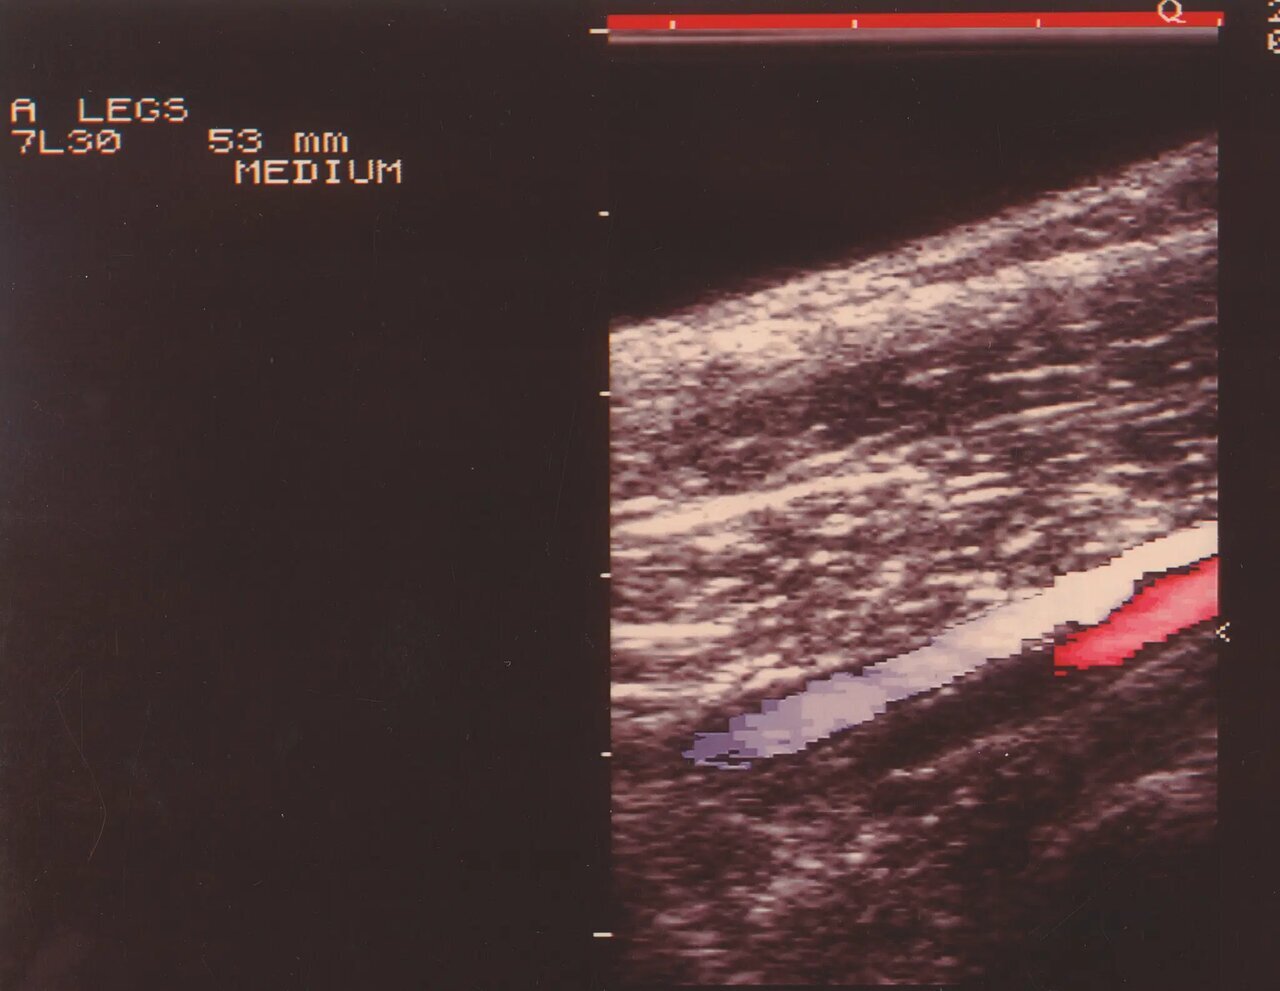

۱۹۹۰

اولین سیستم با فناوری داپلر رنگی؛ که تصویربرداری از جریان خون در عروق، بدون آنژیوگرافی محیطی تهاجمی را برای اولین بار امکانپذیر کرد. این دستگاه به لطف یک ریزپردازنده فوق سریع با ۵۰۰ میلیون عملیات در ثانیه، توانست ویژگیهای آناتومیکی را به صورت سیاه و سفید و جریان خون را به صورت رنگی به طور همزمان نمایش دهد.